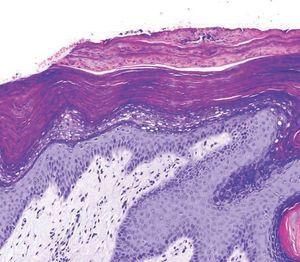

Se le realizó una biopsia de la lesión de la axila izquierda con el resultado de epidermis acantósica con una marcada capa córnea paraqueratósica en la que se mantienen los gránulos de queratohialina en el seno del estrato espinoso. En la dermis papilar se observa un discreto infiltrado linfocitario perivascular. Todo ello compatible con el diagnóstico de paraqueratosis granular (fig. 2).

Figura 2. Epidermis acantósica con una marcada capa córnea paraqueratósica en la que se mantienen los gránulos de queratohialina en el estrato espinoso. En la dermis papilar se observa un discreto infiltrado linfocitario perivascular.